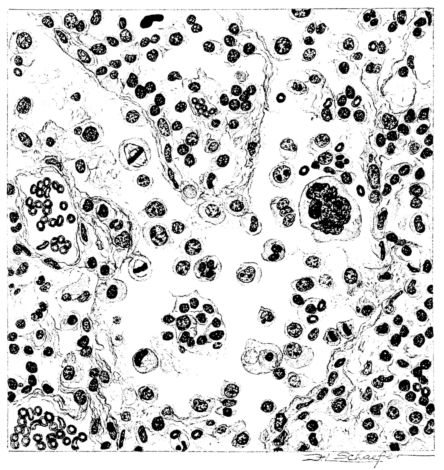

FIG. III. AUTOPSY NO. 90. DRAWING FROM A LESION OF THE TRACHEA (SOMEWHAT OLDER THAN THAT ILLUSTRATED IN FIGURE II). THE MUCOSA IS ENTIRELY LACKING. CONGESTION AND EDEMA ARE THE STRIKING FEATURES IN THE SUBMUCOSA. THE NECROTIZING PROCESS HAS EXTENDED INTO THE MUCUS GLANDS. THIS IS SHOWN IN THE LOWER PICTURE.

The changes are less marked, perhaps, in the trachea than in its finer ramifications. The mucosa is constantly more or less destroyed and large areas, usually focal, are entirely devoid of their epithelial covering. This is replaced by a sparse exudate, composed largely of red blood cells, mucus, a small amount of fibrin, and nuclear fragments (Fig. II). It may dip into the submucosa for a short distance, but usually these indentures are associated with the ducts of the mucous glands into which the inflammatory reaction extends. A more striking feature than the exudate, however, is the edema and the congestion of the submucosa. The loose areolar tissue of the submucosa is spread widely apart, and throughout it distended blood vessels are very conspicuous. Occasionally such a vessel is broken and actual hemorrhage appears in the submucosa. Occasionally, too, the inflammation extends down the duct to the mucous gland itself, and here, also, aplastic inflammatory reaction is evident, inasmuch as the acini now stain intensely red with the cells undifferentiated from each other and specked here and there by broken remains of the dead nuclei (Fig. III). After the disease has continued for a short period, even at the end of five or six days, some regeneration of the epithelial lining may be seen (3) (Fig. IV). But despite this, the acute picture persists, and there goes on, side by side, an attempted repair characterized by epithelial regeneration and the same evidence of acute change. Since the lesion is essentially a superficial one, scars or contractures of any extent are not encountered in the trachea, even in examples of the disease that have ended fatally only after many weeks.[4]